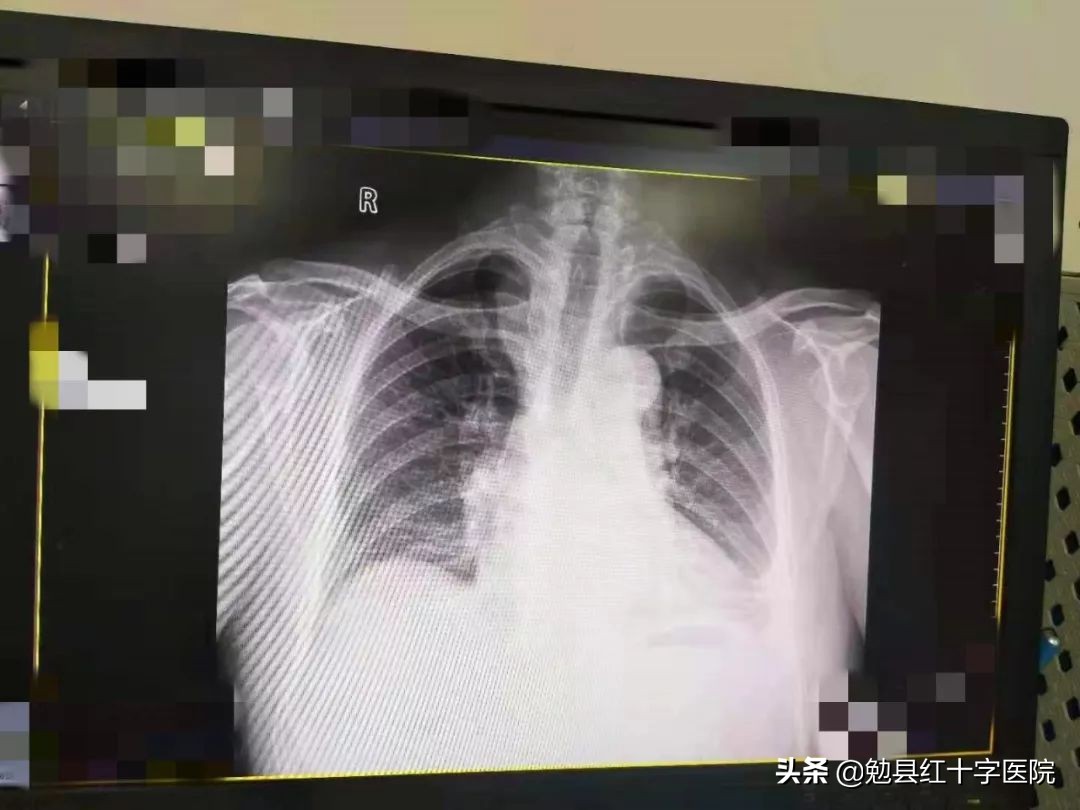

根据患者病史、症状及相关辅助检查,最后确诊为结核性胸膜炎(渗出性)。立即给予了正规抗结核治疗,同时再次行胸腔穿刺术,三天后复查胸片,积液量基本消失,患者各项复查指标恢复正常,顺利出院。

治疗后